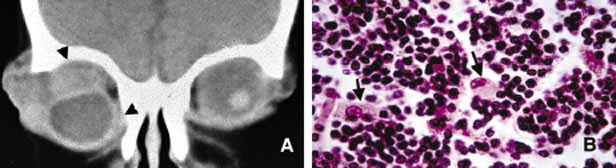

Fig. 7 Orbital tuberculosis. A 2-year-old boy with left orbital tuberculosis (A). Both mother and child had systemic disease. A case of bilateral orbital and perinasal sinus tuberculosis is shown in the coronal CT of a 28-year-old man (B). Note the irregular involvement of the bony tissues of the orbits and the sinuses. C and D show a caseating granuloma (c) and AFB-positive tuberculous bacilli in necrotic inflammation (arrowheads) respectively.